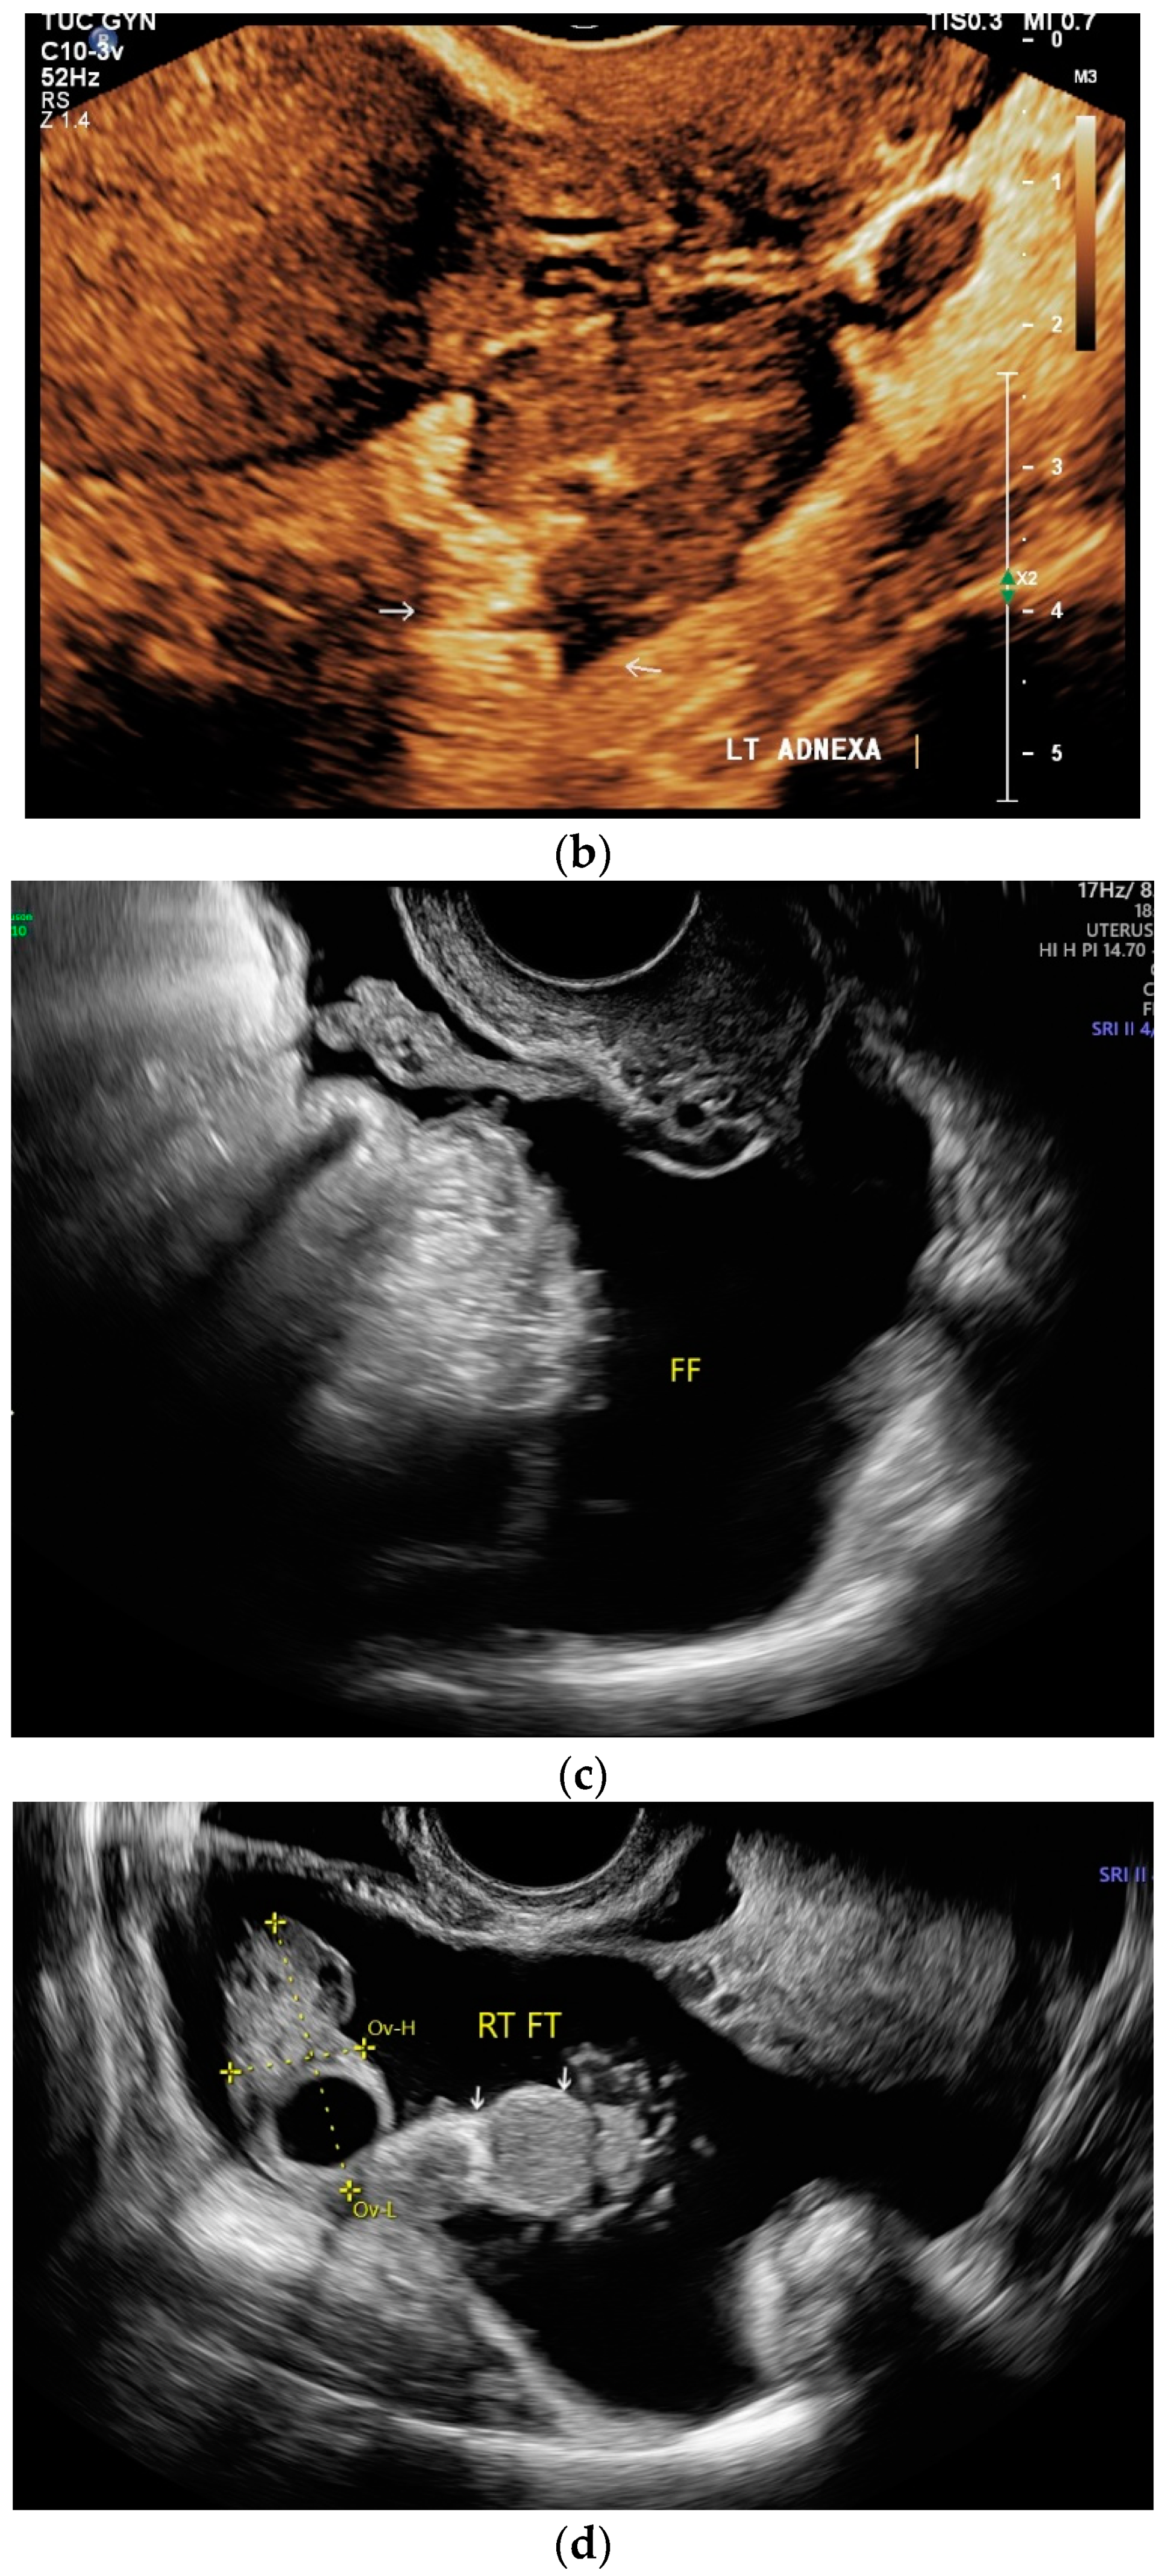

9. Spleen

Spleen involvement usually only occurs in disseminated disease. The manifestations are splenomegaly, hypoechoic micronodular (miliary), or macronodular lesions [8,74], as well as splenic abscesses [75] [Figure 4a–d]. In a group of patients with tuberculosis and mostly advanced HIV infection, 37% had splenic lesions [5]. In 33%, splenic lesions were associated with lymphadenopathy, and 16% each had splenic lesions and ascites or splenic lesions, ascites, and lymphadenopathy. Micronodular lesions may be indistinguishable. If this is suspected, examination with a high-resolution linear transducer is recommended. Using CEUS, splenic lesions in the arterial phase showed a hyperenhancement, followed by either a slow washout or a persistent enhancement in the middle and late parenchymal phase [76]. A fast washout was the exception, but nevertheless was also possible. These exceptional cases would therefore be difficult to differentiate from malignancies. There was also rim-like enhancement with central nonenhancement, like abscesses and septation-like enhancement [76]. Another study using CEUS in splenic manifestations of tuberculosis presented homogeneous enhancement (6.7%), heterogeneous enhancement (63.3%), and nonenhancement (30.0%). Most of the cases showed low enhancement. Among these cases, heterogeneous enhancement was divided into septal enhancement type (21.1%) and marginal enhancement type (78.9%) [77] [Figure 4c–g]. The most important differential diagnoses are non-Hodgkin’s lymphoma and other granulomatous inflammations, such as sarcoidosis, especially in the presence of lymphadenopathy. The splenic lesions must be differentiated from mycotic abscesses, leukemic infiltrates, and metastases. In the meta-analysis conducted by van Hoving et al. [78], splenic lesions as manifestations of abdominal tuberculosis had a broad sensitivity of 13–62% in five studies using B-mode ultrasonography. The specificity was higher, at 86–100%.

Figure 4.

Sonographic and CEUS features of splenic tuberculosis. Sonographic and CEUS features of splenic tuberculosis. Subcapsular splenic lesion (arrow) (a), subcapsular splenic lesion using a linear transducer of 12 MHz (arrows) (b). Histologically confirmed tuberculosis from mediastinal lymph nodes. Multiple small splenic lesions (c). Using CEUS with a linear transducer (9 MHz), these are slightly hypoenhanced in the arterial phase (d), and show a progressive washout in the course of the venous phase (arrows) (e). Subcapsular splenic lesion (arrow) with nonenhanced and hypoenhanced parts and hyperenhanced rims indicate a caseous necrosis (f). In another section, an interrupted spleen capsule (arrow) due to a rupture of the caseous necrosis can be assumed (g).